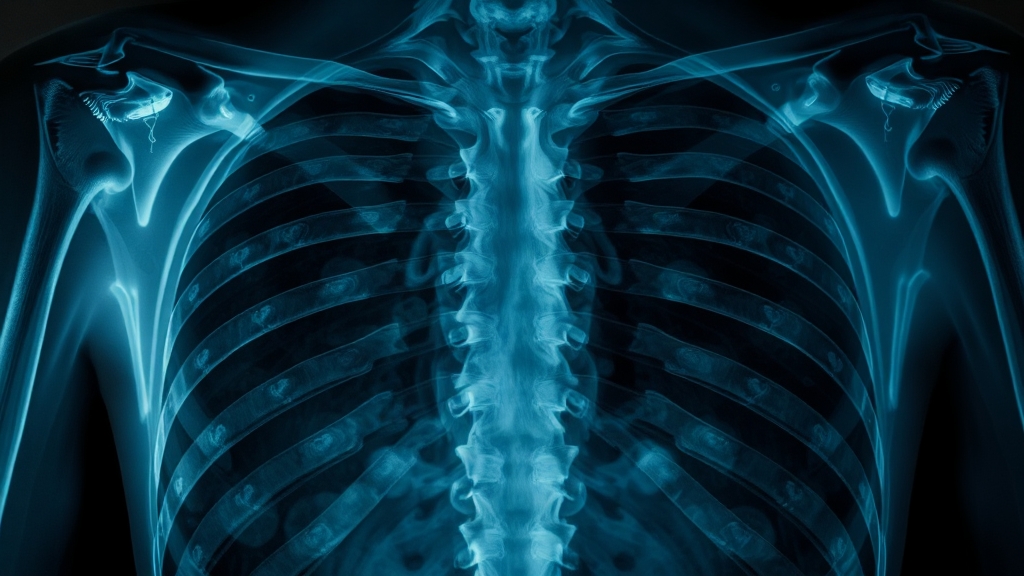

정확한 진단이 중요

갈비뼈 골절이 의심된다면 병원에서 엑스레이 촬영을 통해 진단받아야 해요. 미세 골절은 엑스레이로 확인하기 어려울 수 있어, 초음파나 CT 검사가 필요할 수도 있답니다. 정확한 진단을 통해 적절한 치료 계획을 세우는 것이 중요해요.